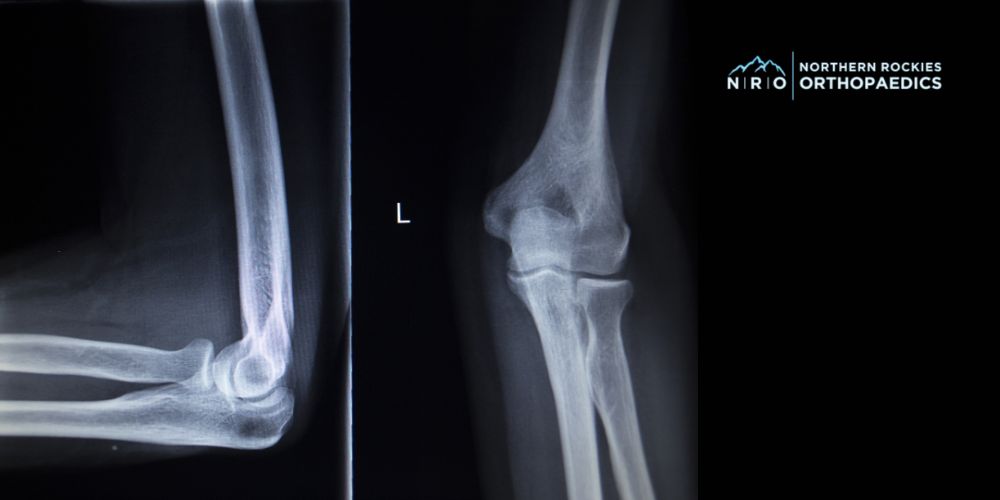

Elbow Treatments in Missoula, Montana

Advanced Orthopedic Solutions for Elbow Pain in Missoula

We treat a wide range of elbow conditions, including overuse injuries, ulnar nerve compression, joint stiffness, tendon irritation, and more. Our Missoula elbow specialists use the latest diagnostic tools and treatment techniques to reduce inflammation, relieve pain, and restore natural movement in the elbow joint.